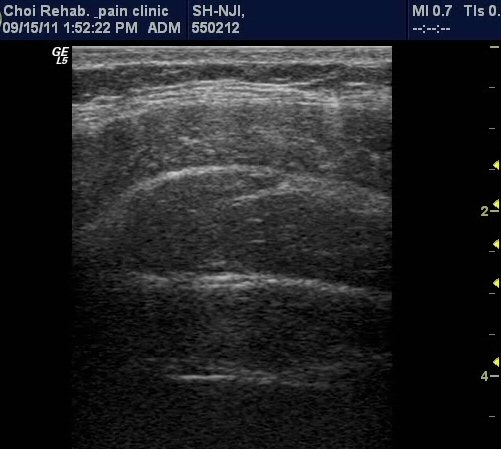

°¡Àå ½ÉºÎ¿¡ Ⱦº¹±ÙÀÌ °üÂûµÇ°í ÀÖ´Ù(±×¸² 1). ¼Òº¯À» ÂüÀ¸¼¼¿ä, °ñ¹ÝÀ» ¸Ó¸®ÂÊÀ¸·Î ¿Ã¸®¼¼¿ä,

¹è²ÅÀ» ¹Ù´ÚÀ¸·Î ³»¸®¼¼¿ä µîÀ¸·Î À¯µµÇÑ »óÅ¿¡¼­ Ⱦº¹±ÙÀÇ µÎ²²°¡ µÎ²¨¿ö Áø »óÅÂ(±×¸² 2, 3,

µ¿¿µ»ó 1, 2). ŽÃËÀÚ¸¦ Ä¡°ñ »óºÎ(ŽÃËÀÚ 2)¿¡ ´ë°í ¹æ±¤À» °üÂûÇÑ »óÅ¿¡¼­ °ñ¹Ý ¹Ù´ÚÀÇ ±ÙÀ°À»

¼öÃàÇÏ¿© ¹æ±¤À» ¸Ó¸® ÂÊÀ¸·Î µé¾î ¿Ã¸®´Â ¸ð½À(µ¿¿µ»ó3).